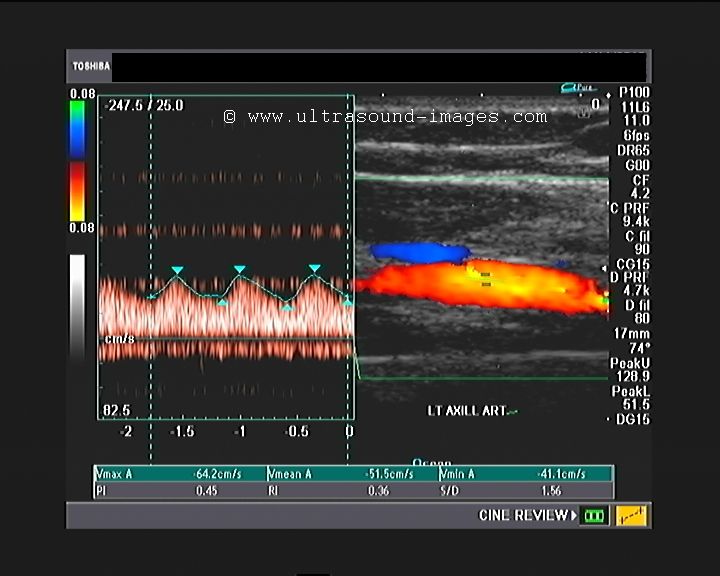

Pulseless disease- color Doppler imaging of upper limb

This is an interesting case of a 25-year-old woman with pulse less disease of both upper limbs. Colour Doppler ultrasound of the left upper limb showed dampened flow in the entire arterial system.

Spectral Doppler showed absence of tri phasic pattern with an almost venous flow pattern in the axillary artery, the brachial artery and the radial and ulnar arteries.

What is your diagnosis based on these colour Doppler images of the left upper limb?